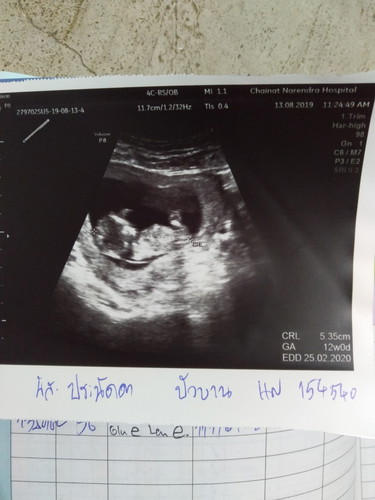

12สัปดา

น้องตัวเล็กมั้ยคะ

นี่จ้า

ปกติจ้า